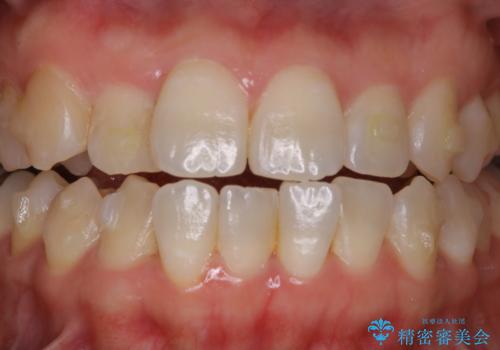

60分のPMTCで歯の黄ばみをきれいに除去

- 年末年始と忙しく、なかなか歯のケアがしっかりできなかった事と着色も気になるとのことで来院されました。PMTC60分コースを行いました。

- 1万円+tax費用は治療当時の料金となります